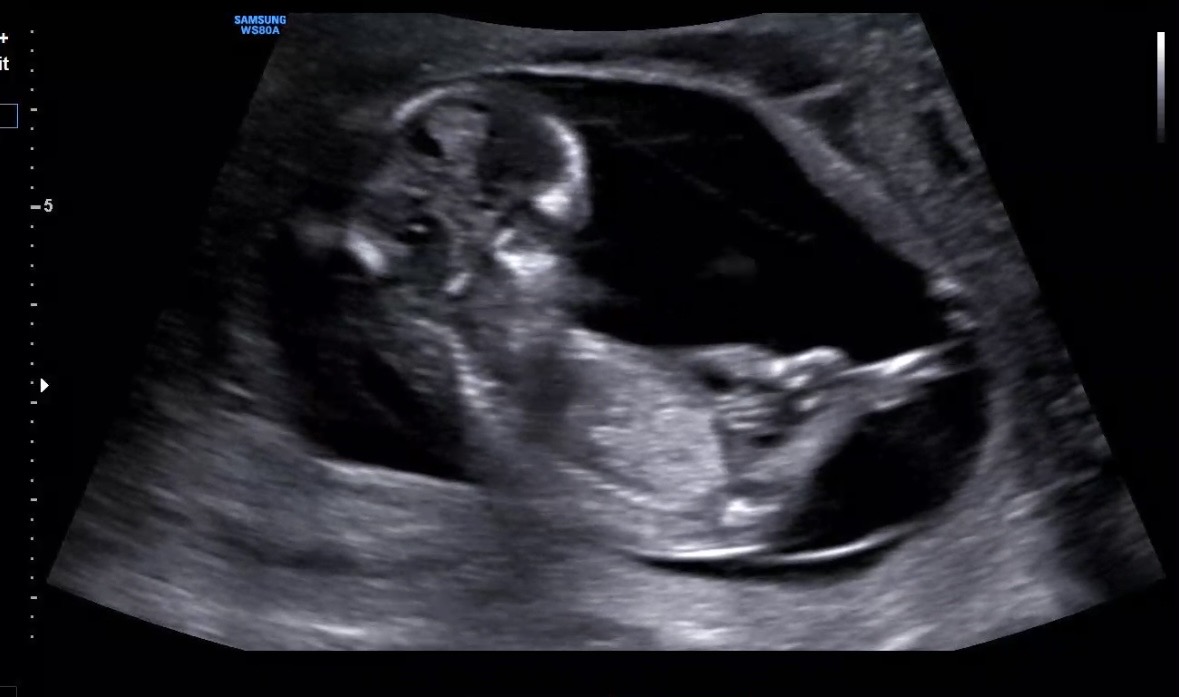

빌리 ai로 성별 예측해 보셨나요?? 정확도가 어떤지 궁금해요~~ 추가로 저희 아이 성별은 어때보이세요??

초음파 사진을 올리면 AI가 무료로 예측해줘요